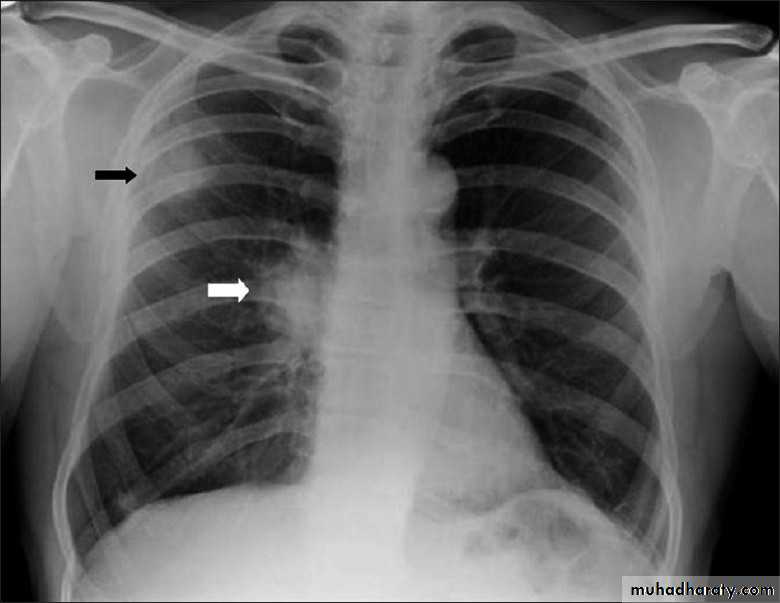

Radiolucent area devoid of lung markings in the upper left lung

Visible viseral pleural edge as very thin sharp white lineRadiolucent area devoid of lung markings in the upper left lung

Visible viseral pleural edge as very thin sharp white linePneumothorax

Radiolucent area devoid of lung markings in the periphry of the right lung with visible viseral pleural edge

The mediastinum is pushed to the opposite side

Tension pneumothorax

Right pneumothorax

Radiolucent area devoid of lung markings in the area of the left lung with visible viseral pleural edge.Tension Pneumothorax

Radiolucent area devoid of lung markings in the area of the right lung with visible viseral pleural edge. The mediastinum is pushed to the opposite side